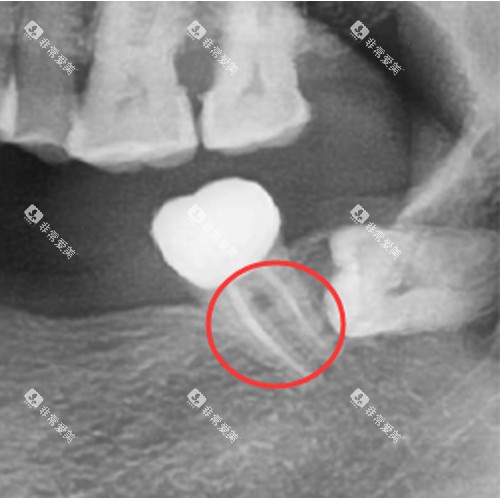

科尔口腔引进了一系列国内外可靠的牙科设备,如智能化口腔全景机、激光治疗仪等。

这些设备能够为医生提供更加更准的诊断信息,提高治疗的结果和效率。

例如,智能化口腔全景机能够快速、清晰地拍摄口腔全景图像,帮助医生超全了解患者的口腔状况。

可靠的技术和设备是确保治疗结果的重要因素。

选择牙科诊所时,要了解其是否采用了可靠的牙科技术和设备。

例如,智能化诊断技术、不痛治疗技术等。